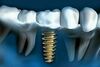

IMPLANTOLOGIE